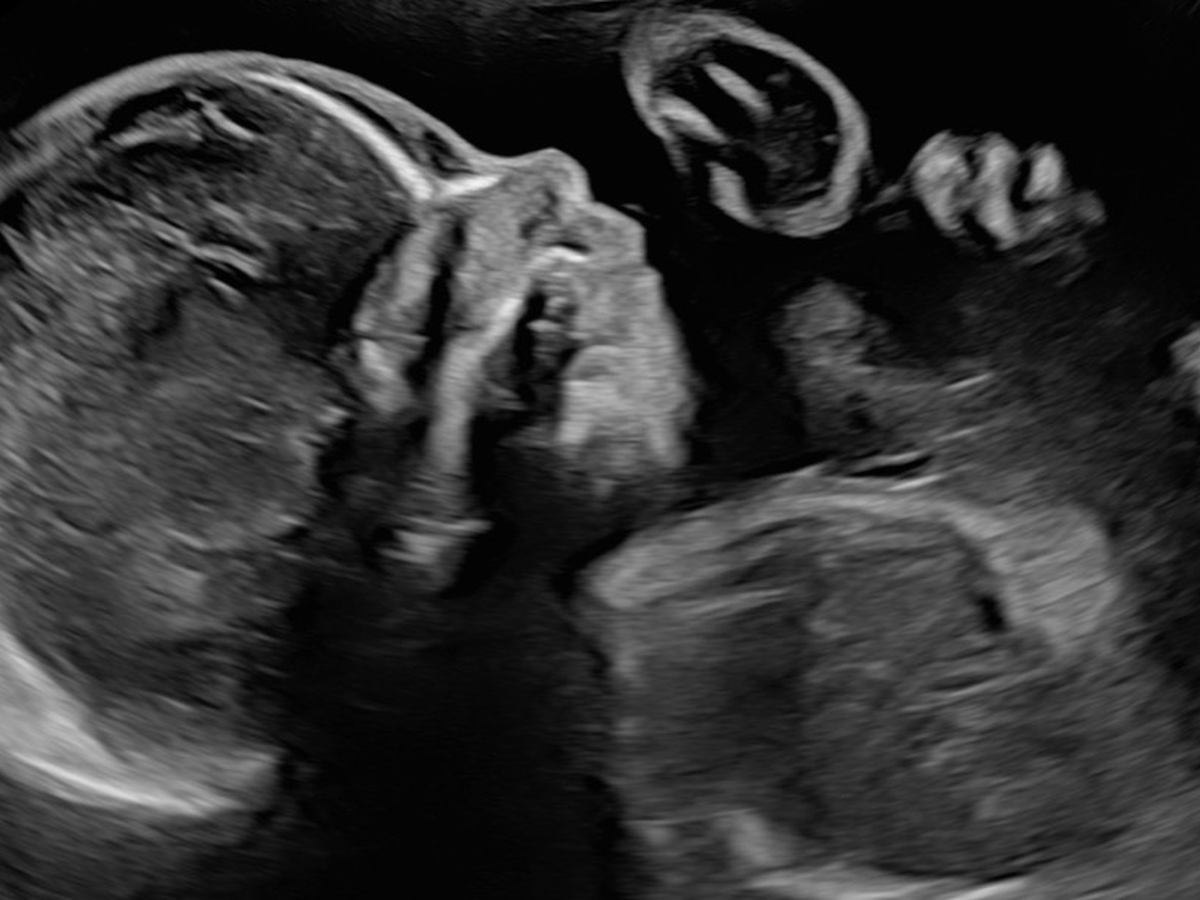

For a while, everything seemed normal. Our doctor’s appointments went smoothly, and each ultrasound filled our hearts with hope and excitement. But as time went on, we received news that changed everything.

After a detailed ultrasound, doctors noticed some serious concerns. We were referred to specialists and eventually sent to UCSF in San Francisco to see some of the best experts in the country. Through countless tests — including fetal heart echos, in-depth ultrasounds, and an MRI — we learned that our sweet baby boy faces many severe complications:

• He has no right lung and only about 10% of his left lung.

• His heart lacks the veins and valves that would normally connect to the right lung and is pushed all the way to the right side of his chest.

• His left kidney is located in his pelvis instead of his abdomen.

• His jawbone is very narrow, causing his tongue to sit farther back in his throat.

• And he has no gallbladder.